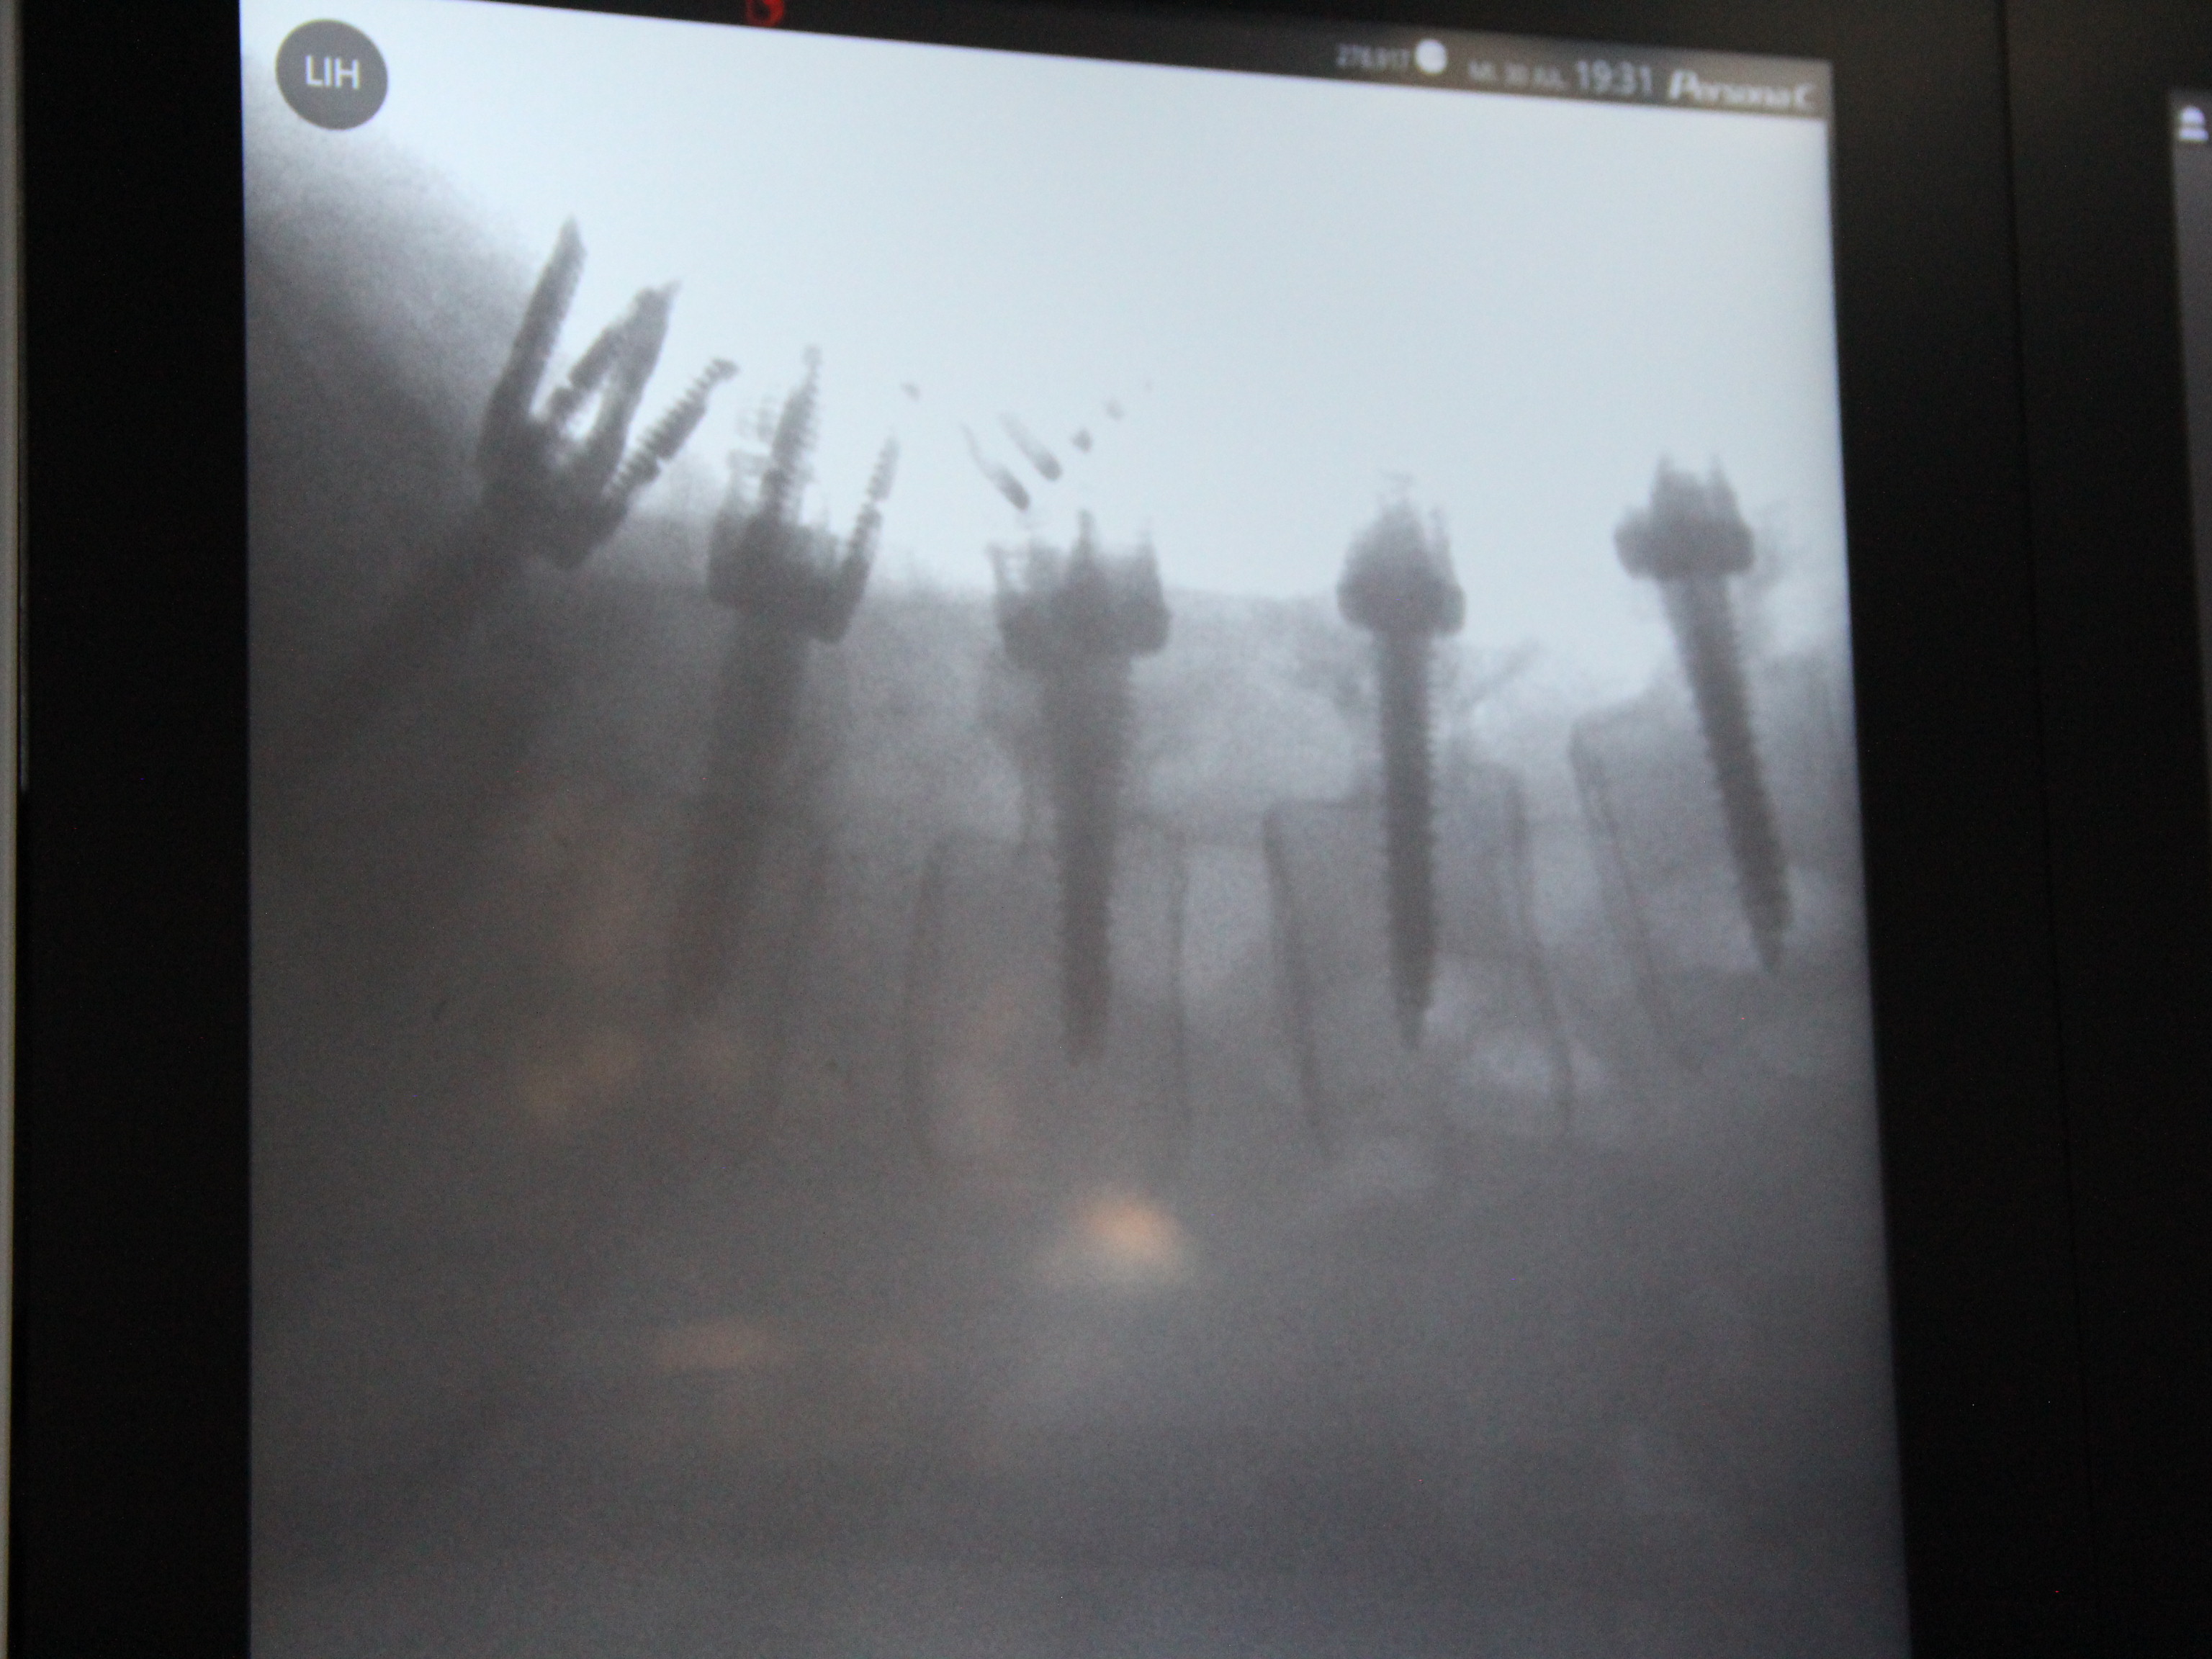

SURGERIES

RESULTS